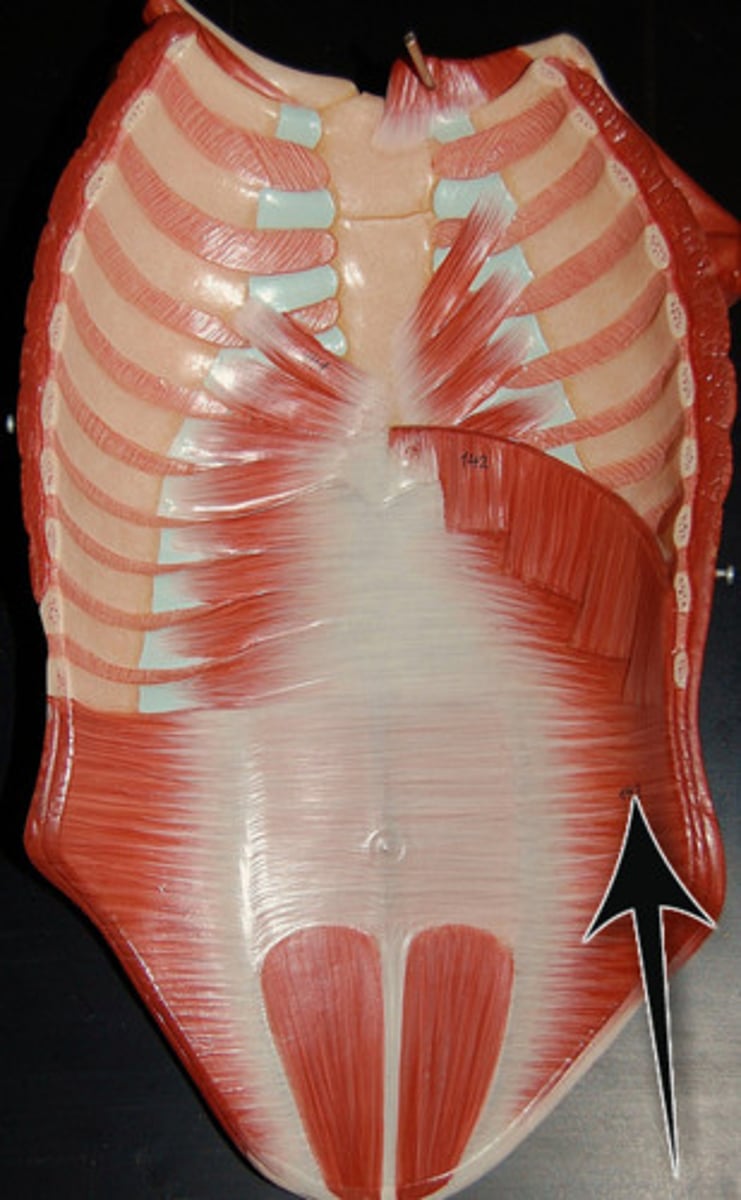

Rectus Abdominis

External Obliques

Internal Obliques

Transversus Abdominis

Linea Alba

Tendinous Inscriptions

Pectoralis Major

Serratus Anterior